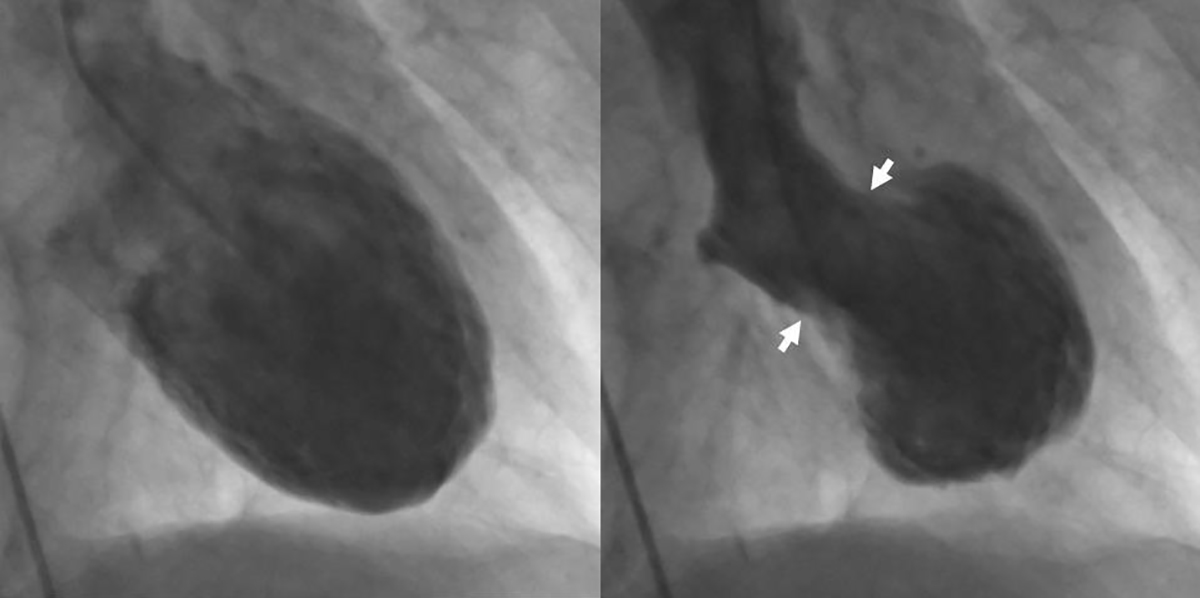

The patient displayed normal coronary arteries on angiography with no blockages but was diagnosed with takotsubo cardiomyopathy (TCM).

Takotsubo cardiomyopathy is a transient cardiac condition that involves left ventricular apical akinesis (or ballooning) that can mimic acute ST-elevation myocardial infarction (STEMI). Because it is typically associated with significant emotional distress it is sometimes referred to as “broken heart syndrome” or “stress cardiomyopathy”.

The Japanese cardiologist who first described takotsubo cardiomyopathy in 1990 noticed that the left ventriculogram took on the shape of a fishing pot used to trap octopus. In Japanese name for “octopus pot” is “tako tsubo.”

Patients with TCM typically present with chest pain and shortness of breath and ST-segment elevation on the 12-lead ECG. This can be accompanied by a rise and fall of cardiac biomarkers consistent with acute myocardial infarction. As seen in the above case, no acute thrombotic lesions are noted with angiography. Diagnostically, apical ballooning of the left ventricle is present.